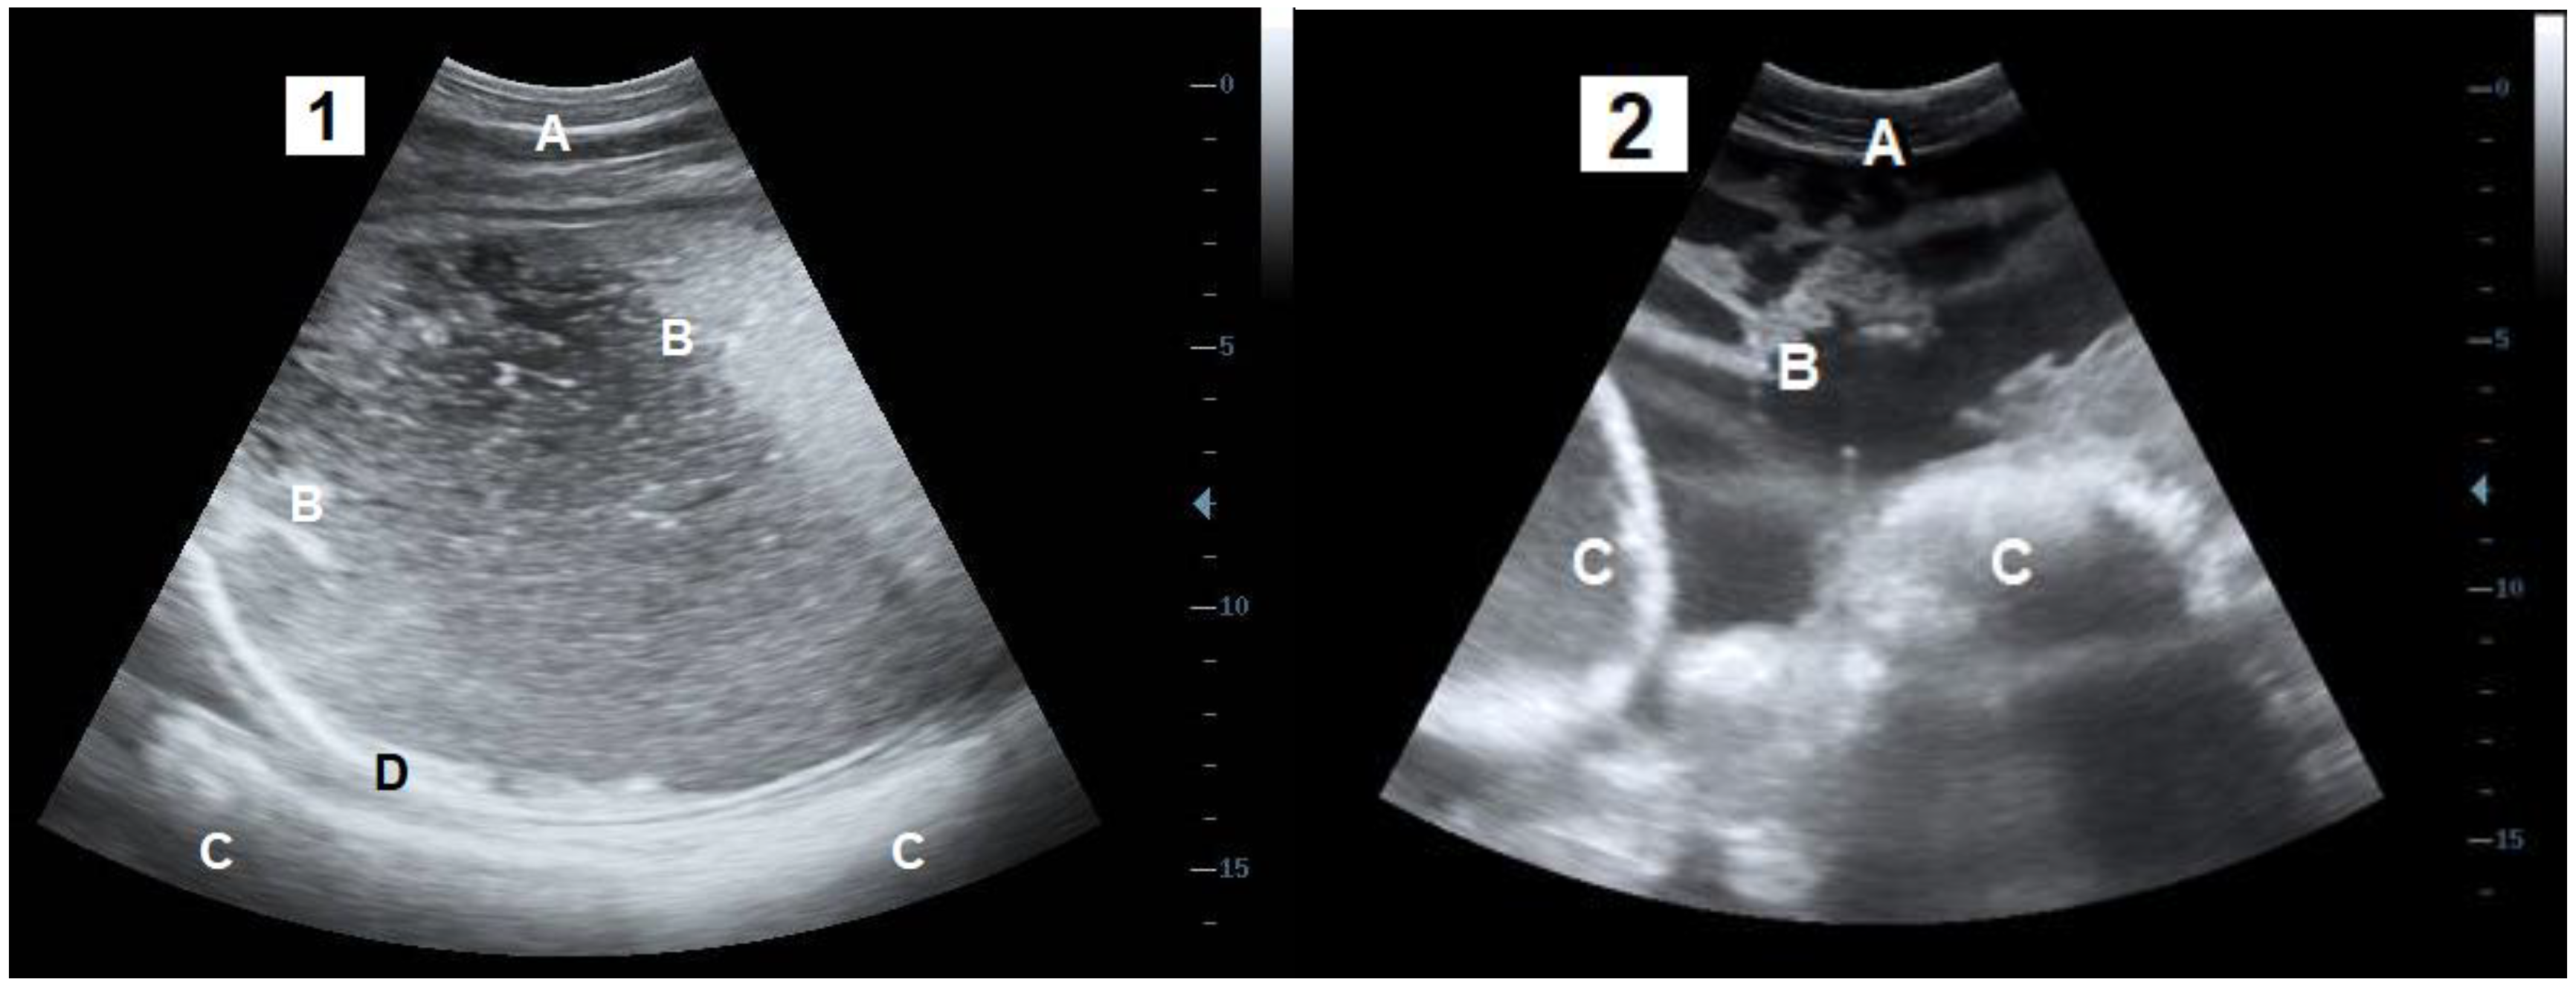

- Braun, U.; Pusterla, N.; Anliker, H. Ultrasonographic findings in three cows with peritonitis in the left flank region. Vet. Rec. 1998, 142, 338–340. [Google Scholar] [CrossRef] [PubMed]

- Braun, U. Ultrasound as a decision-making tool in abdominal surgery in cows. Vet. Clin. Food Anim. Pract. 2005, 21, 33–53. [Google Scholar] [CrossRef] [PubMed]